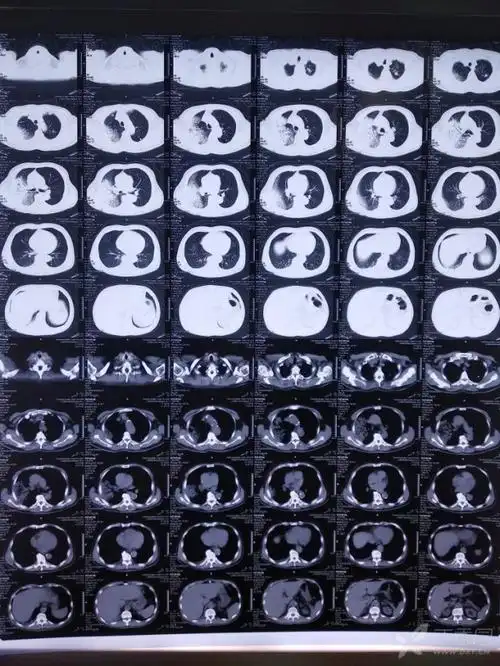

肺炎病例讨论